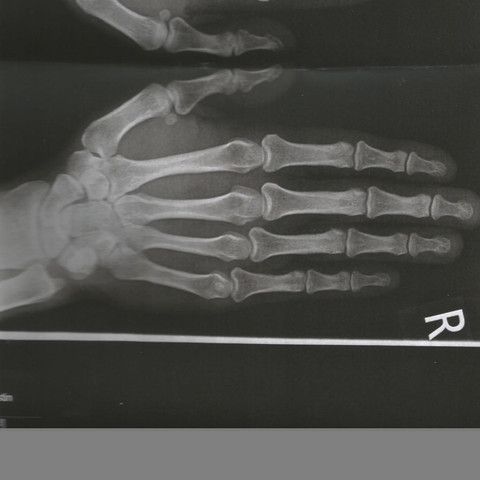

Trotzdem kann man den Gelenkverschleiß und die ausbleibende Regeneration der dämpfenden Knorpelschicht. Als Heberden-Arthrose bezeichnet man einen Gelenkverschleiß der Daumen- und Fingerendgelenke. Wie kann Ihr Arzt die Arthrose untersuchen?